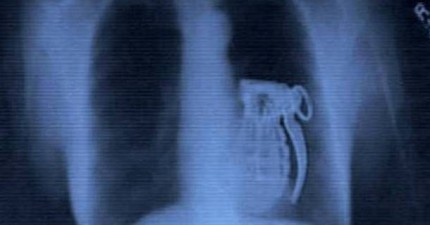

24件曾經在人體裡發現到的最驚奇的物品。